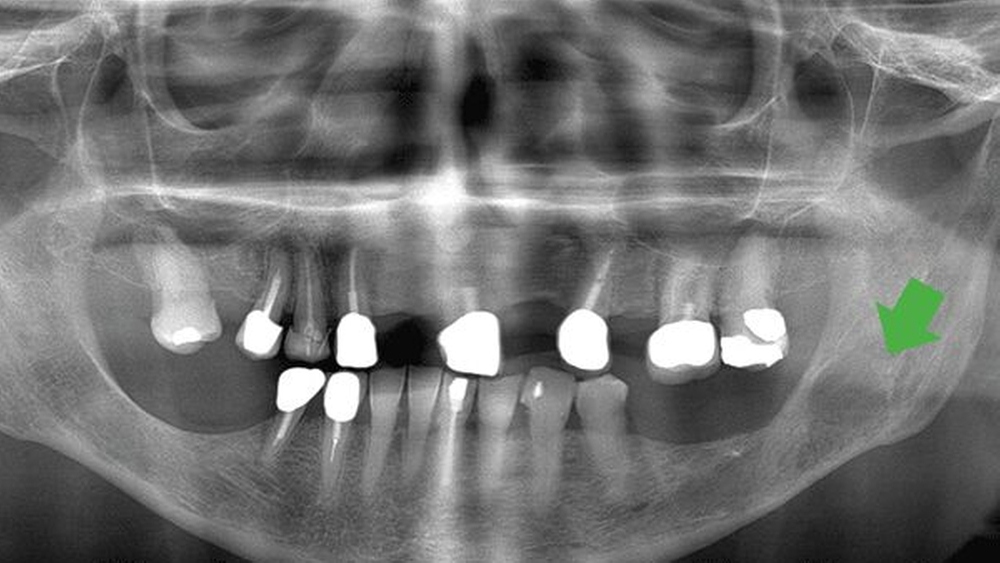

Der extraorale Untersuchungsbefund ist unauffällig. Enoral ist eine fluktuierende Schwellung im Bereich des zahnlosen Alveolarkamms des linken Unterkiefers tastbar. Im angefertigten Orthopantomogramm (OPTG) ist eine zystische Raumforderung im Bereich des Unterkiefers zu erkennen (Abbildung 1). In der anschließenden dreidimensionalen Bildgebung (CT) stellt sich eine glatt berandete, zystische Raumforderung im Bereich des linken Kieferwinkels dar (Abbildung 2).